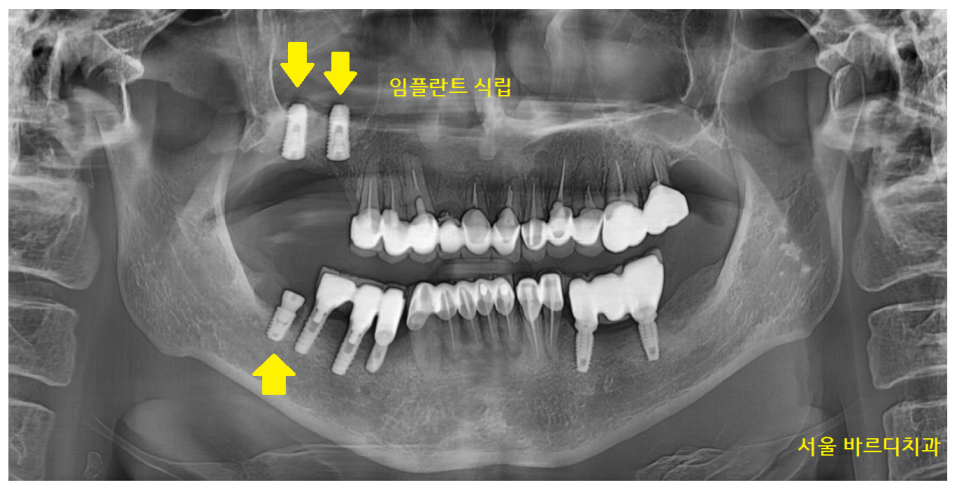

23.09.08

명일동 치과 임플란트 수술 후 사진입니다.

특히나 윗니 치아의 경우

상악동 거상술까지 진행했습니다.

뿌리 염증으로 잇몸 뼈가 녹다 보니

부족한 뼈를 이식해 주는 것이 필요했어요.